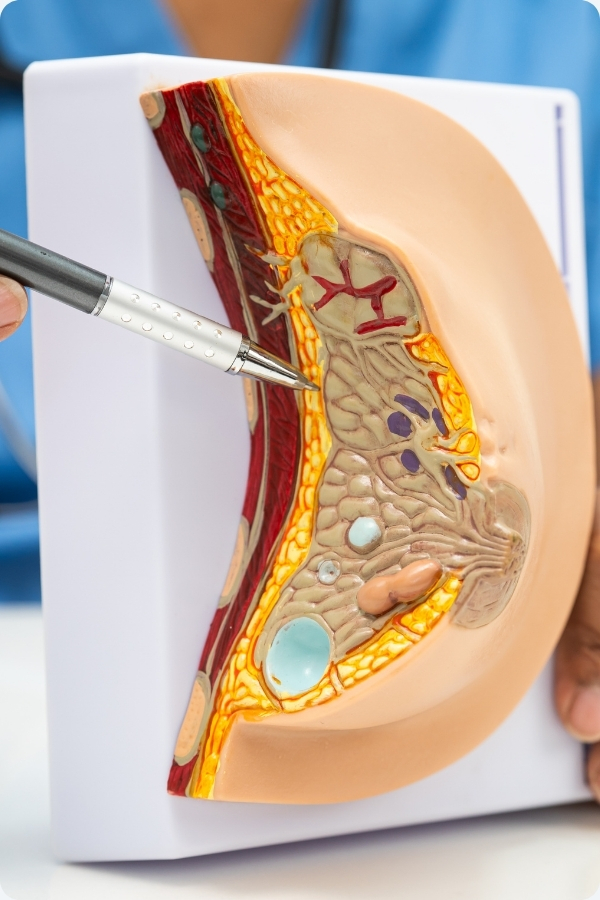

Meme büyütme ameliyatı nedir?

Memeler, yapısal olarak veya değişik nedenlerle (travma, yanık, kanser cerrahisi, enfeksiyon gibi) küçük olabilir. Bir meme diğerinden daha küçük, asimetrik olabilir. Her iki memenin eşit hale getirilmesi yada hacminin arttırılması için meme içersine protez koyularak yapılan ameliyatlara meme büyütme ameliyatları denir.Ancak günümüzde konsept olarak tek başına memeyi büyütme değil, memeyi yeniden şekillendirme , vücut oranlarına uygun bir forma sokma amaçlanıyor.

Meme büyütme operasyonlarında 3 değişik giriş yeri vardır. Bunlar uzunluğu 4-5 cm olabilen koltukaltı kesisi (transaksiller), meme ucu çevresi (periareolar) ve meme altı kıvrımı (inframamar) kesileridir. Bunların her birinin ayrı ayrı avantajları ve dezavatajları olabilir. Cerrah, operasyon öncesi muayenesinde hastanın vücut şekli ve yapısına; meme dokusu miktarına ve meme derisi elastik özelliklerine göre protez yerleşim yerini belirler.

Operasyon ne kadar sürer ve protez nereye yerleştirilir?

Ameliyat genel anesteziyle hastane koşullarında yapılır, yaklaşık 2 saat sürer. Silikon protezler göğüs duvarı kas tabakası ile meme dokusu arasına, yani meme dokusunun hemen altına (sub glandüler); kas kılıfının kalın zar tabakası altına (subfasyal) ya da direkt olarak kas altına (sub musküler) yerleştirilir. Meme dokusunun yapısına, deri kalitesine, elastikiyetine ve meme dokusu kalınlığına göre implantların yerleştirileceği yer belirlenir. Bazı durumlarda protez, üst tarafta yarısı kas altına, alt tarafta yarısı meme dokusu altına (dual plane) yerleştirilebilir.